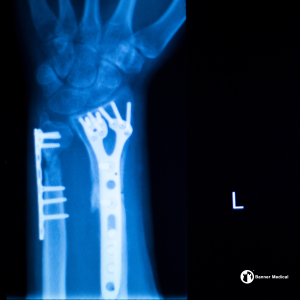

Medical‑grade titanium alloys such as Ti‑6Al‑4V and Ti‑6Al‑4V ELI are commonly used in orthopedic implants, spinal fixation devices, and trauma hardware. These alloys are valued for their fatigue resistance and ability to support osseointegration—helping implants bond effectively with bone tissue.

Manufacturers serving orthopedic clusters in Warsaw, IN, Minneapolis, MN, and throughout the Midwest rely on titanium for hip stems, bone screws, spinal rods, and fracture fixation systems. In California’s medical technology market, titanium is also widely used in next‑generation implant designs where lightweight strength and long‑term performance are essential.